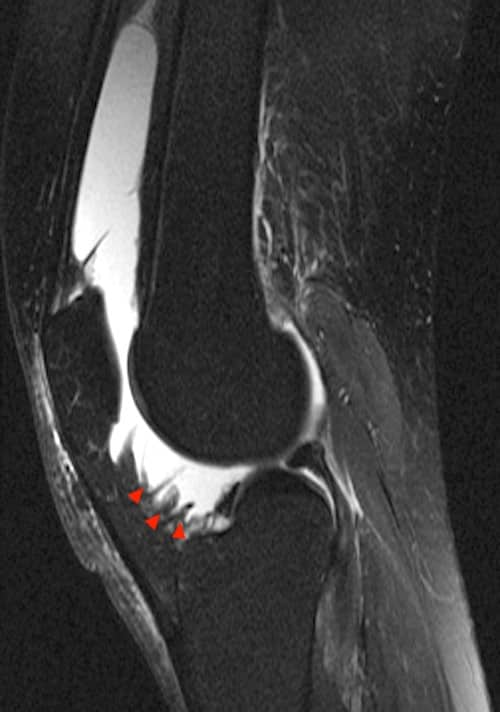

Oligoarthritis Juvenile Idiopathic Arthritis (JIA)

| MRI Hand | MRI Knee |